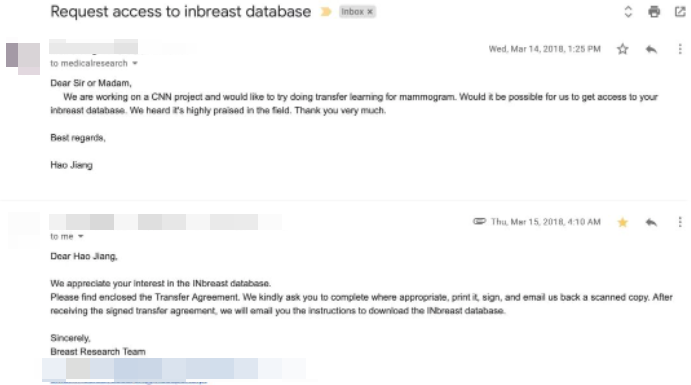

然后,他为了取得巴塞罗那大学的非公开资源——乳腺癌数据集,还特地写了封邮件求得许可。

当时 coolwulf 发送的请求邮件 ▼